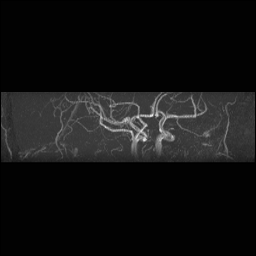

Circle of Willis, projections

For Circle of Willis projection images:

View #2